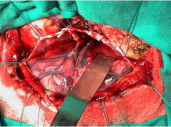

Learn MoreTumours and Cysts

High grade, low grade, benign and non-neoplastic mass lesions of the brain and spine in adults and children